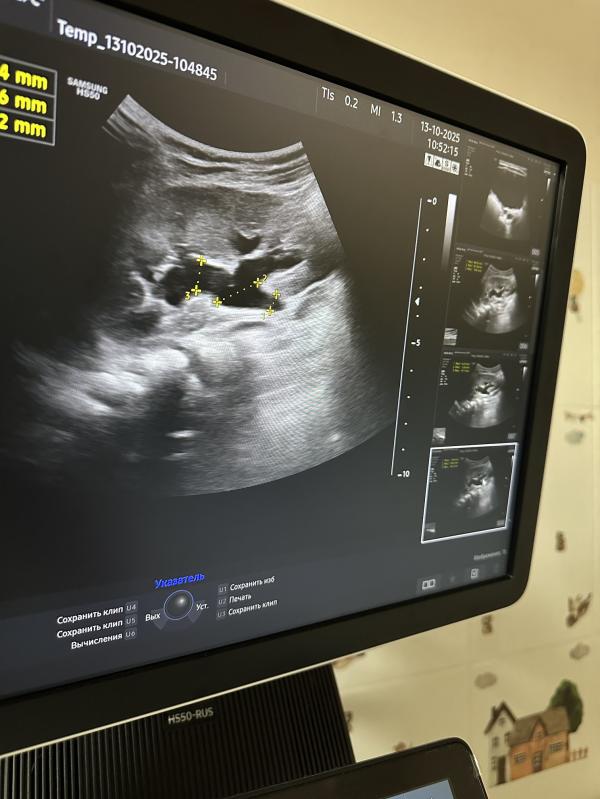

Пациентке всего лишь два года. Некоторое время назад мама заметила незначительные следы крови на нижнем белье девочки и незамедлительно обратилась к специалисту-гинекологу. При проведении ультразвукового исследования органов малого таза патология матки и яичников исключена, мы обратили внимание на некоторые важные нюансы: присутствие взвеси в мочевом пузыре и расширение левого мочеточника.

Последующее дополнительное исследование позволило детально рассмотреть левую почку, где обнаружились существенные отклонения: выраженное расширение лоханки, чашечек и мочеточника, а также истончение почечной паренхимы. Подобные изменения свидетельствуют о длительно протекающем патологическом процессе, приводящем к нарушению функций органа.